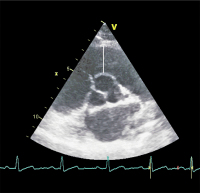

Rechter Ventrikel

Abbildung 3: Vermessung der Wandstärke des rechten Ventrikels von subkostal im B-Bild am Ende der Diastole.